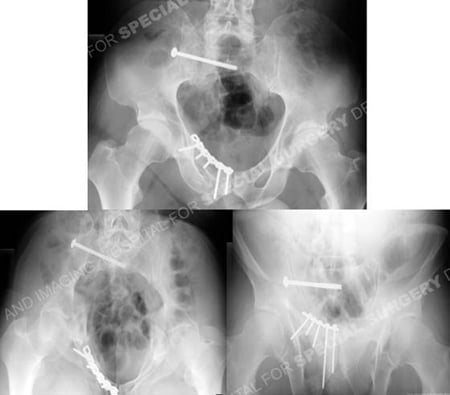

Postoperative anteroposterior pelvic radiograph and CT scan image illustrating acceptable reduction and placement of hardware.

Postoperative radiographs at 6 months demonstrating healed pelvic fractures.